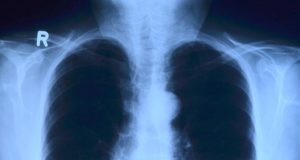

The Danish study titled, “An RCT of acute health effects in COPD-patients after passive vape exposure from e-cigarettes,” looked into the effects of short-term passive vape exposure among individuals with mild to moderate COPD. The 16 non-smoking COPD-patients (mean age 68) were randomly exposed to vapour for 2 sessions, each of which lasted 4 hours. … Continue reading New Study Links Vapour Exposure to Acute COPD Symptoms